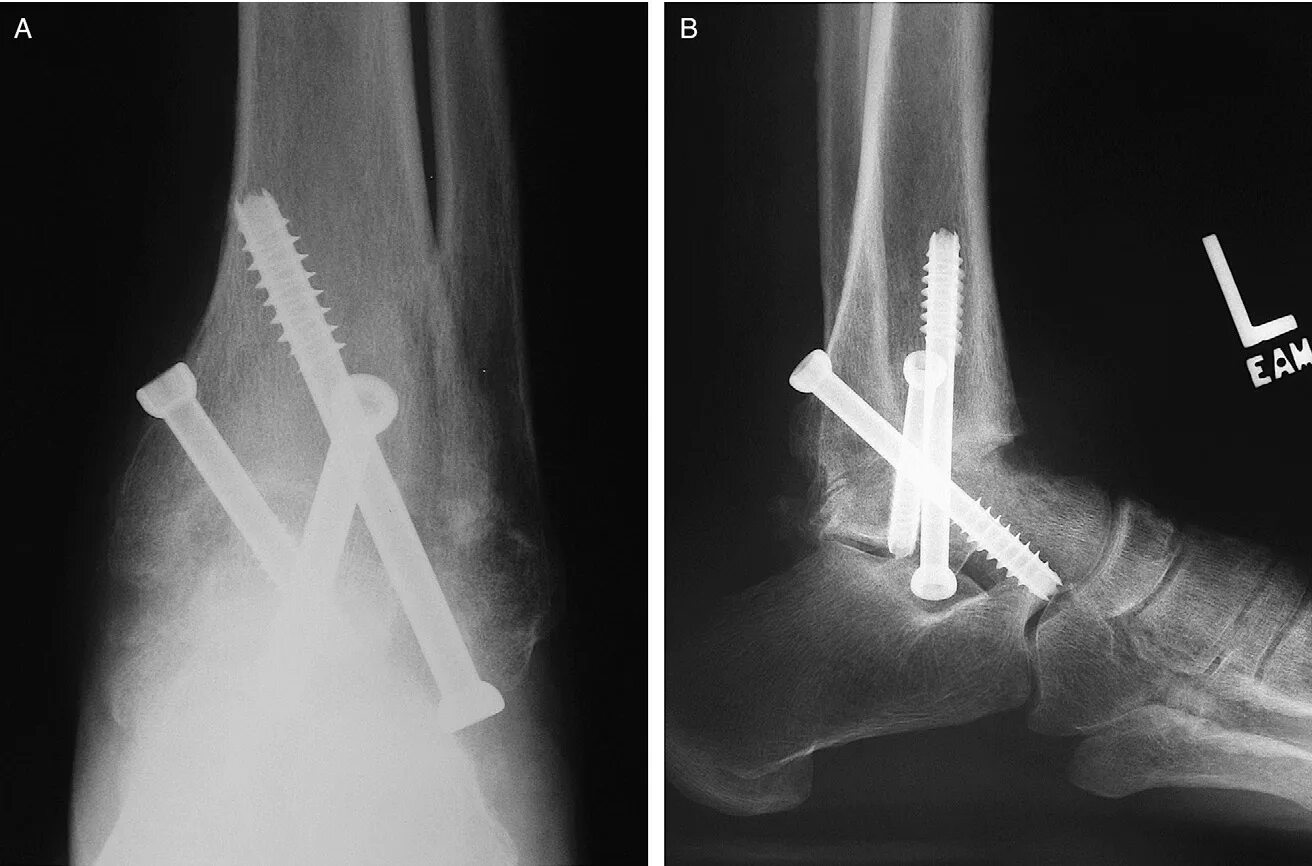

Артродез форум